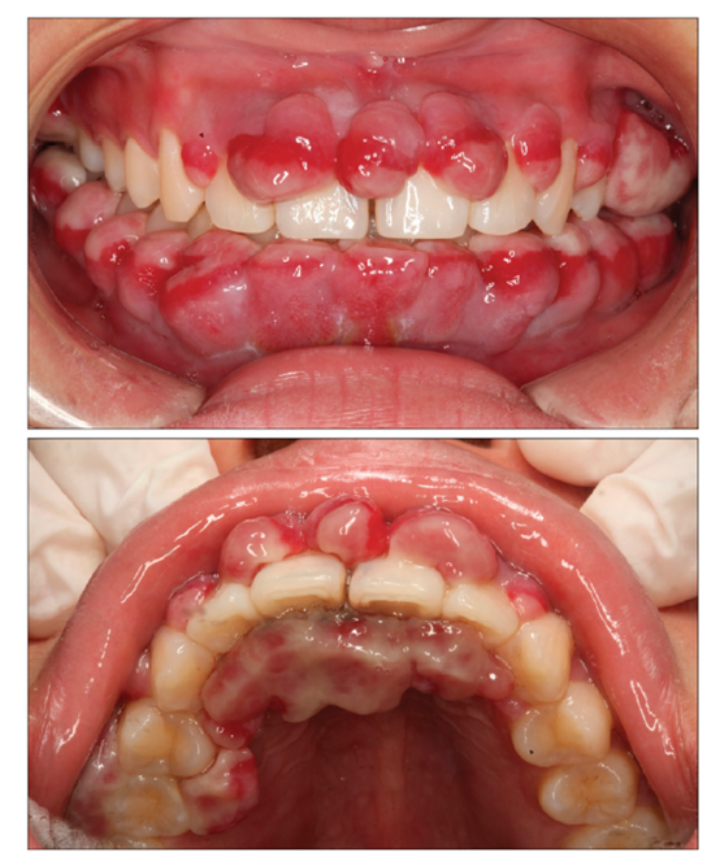

妊娠期牙龈增生

一些女性在怀孕之后,由于孕激素水平升高、血管扩张的原因,牙龈容易出现红肿,甚至牙龈增生的症状。比如在急性龈乳头炎发作时,牙龈乳头发红、肿胀,也可能痛得厉害。